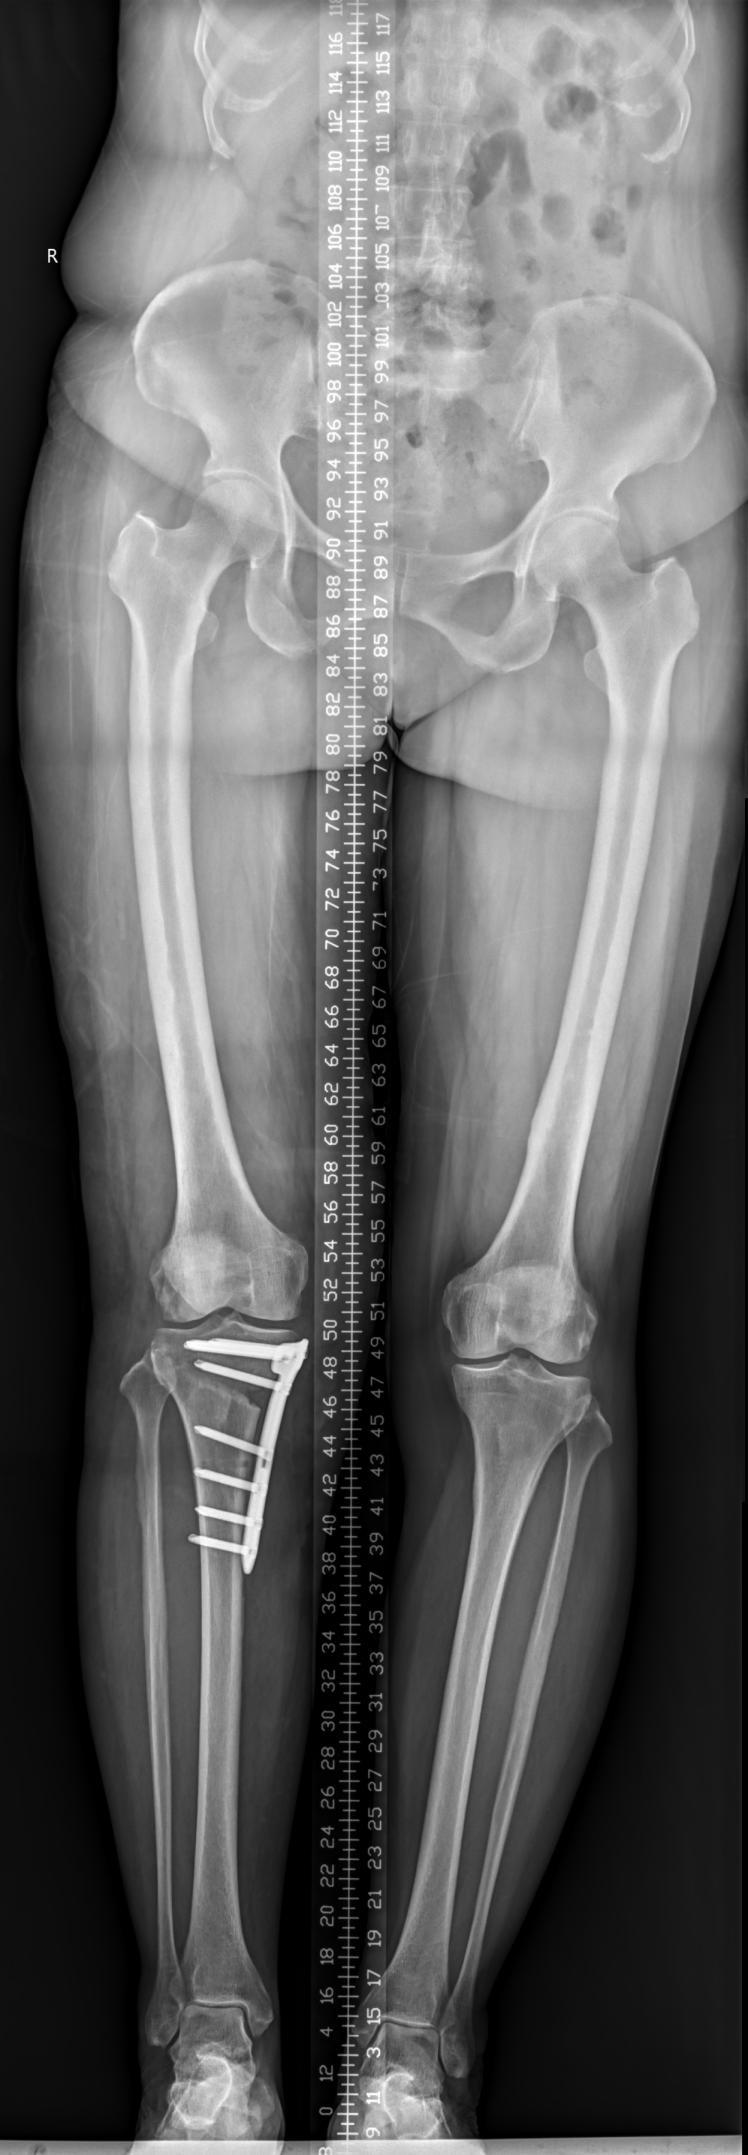

该科擅长对膝关节严重创伤(包括股骨远端骨折、髌骨骨折、胫骨平台骨折等)、膝骨关节炎阶梯化治疗、保膝治疗、膝关节微创单髁置换术、全膝关节置换术、膝关节翻修术具有丰富的临床诊疗经验,追求微创、无痛、快速康复。